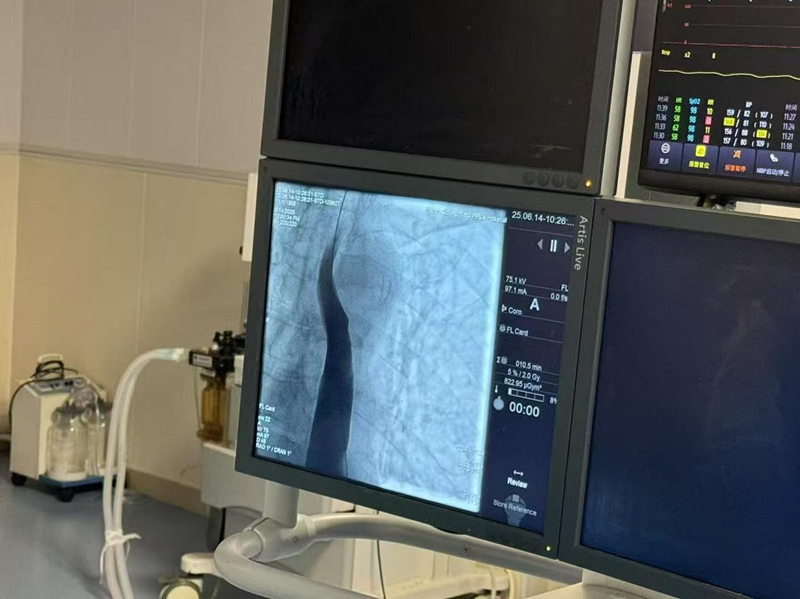

术前造影提示吻合口明显狭窄

术中DSA直视下扩张

术后造影提示梗阻解除